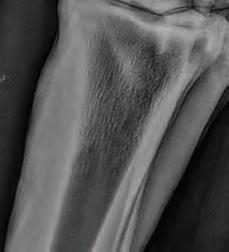

Bilateral hind cannon radiographs of X XXXX XXXXXX were taken on 14th April 21 and again 17th May 21 and 14th June 21. Initial radiographs showed a 32mm longitudinal non displaced left mid cannon saucer fracture extending 6mm into the dorsal cortex and a 44mm longitudinal displaced fracture right mid cannon 5.5mm in depth mid dorsal cortex associated proximally with a 27mm x 6.5mm secondary fracture (see right). Initially, surgical removal was recommended of the R H fracture fragment.

A second series was taken on 17th May and third series on 14th June see right. Both fractures have attached and integrated with the parent bone with minor surface

enthesophyte formation and periosteal activity evident.

R H 17.05.21 R H 14.04.21

R H 14.06.21